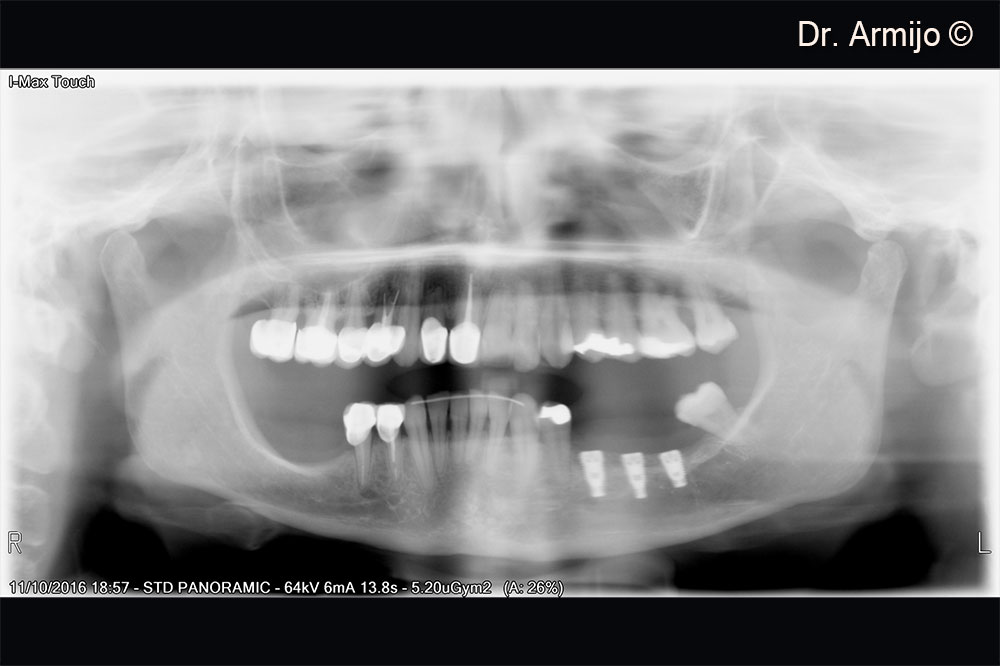

Initial orthopantomography

Post-surgery X-ray of implants